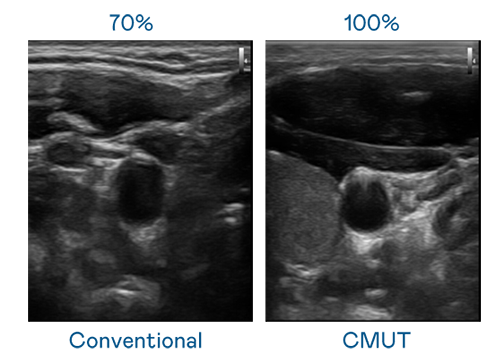

CMUT 技术是一种用电容式微机电元件来产生超音波讯号的技术。与传统 PZT 压电式技术相比,CMUT 频宽增加 30%,更宽频的超音波讯号让影像解析度大幅提升,是实现高影像品质医疗超音波扫描、促进精准医疗发展的关键技术。

超音波影像的解析度高低,首先取决于探头能发出的讯号频宽。尊龙凯时人生就是博 CMUT 可提供高清晰的超音波讯号,提供高频宽、高灵敏度、影像纹理细节更高的超音波影像,协助医护人员缩短影像判读时间及利用精准的医疗影像进行诊断。